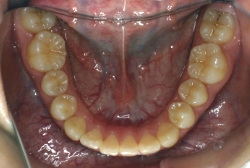

歯科矯正用アンカースクリューを用いた症例(骨格性反対咬合 非抜歯治療)

「ものがうまく噛めない」という主訴で来院したケースです。診断の結果、「骨格性反対咬合に伴う咬合不良+軽度叢生」と判明しました。原因としては特に下顎の左側が過成長したため、骨格性反対咬合になり、特に左側での噛み合わせが非常に悪くなっていると診断しました。初診時の写真を見ると、上下の正中線の大きなズレ、左側の噛み合わせの不良がはっきり分かります(黄色の矢印と緑の矢印は一致しているのが正しい状態です)。

そもそも、このような状態となっているのは骨の大きさに問題があるため生じていますので、場合によっては、「外科矯正」によって下顎の骨を外科的に縮めることで修正します。患者様が外科矯正をご希望されない場合は、従来ですと上下左右の小臼歯抜歯を行い矯正するのが普通です。

今回の患者様の場合は、「外科」も「小臼歯抜歯」も拒否されましたので、歯科矯正用アンカースクリュー(以下 アンカースクリュー)を用いて、下顎の歯列全体を後方に下げるという方法を取りました。

治療中の写真で、アンカースクリューより歯を後ろへ牽引しているのがお分かりいただけるかと思います。牽引を1年ほど続け、途中補助的に上下にゴムをかける(これを顎間ゴムと言います)手法なども追加し、全体で21ヶ月で治療を終えることが出来ました。

結局歯の本数を減らすことなく、すべてご自分の歯を残して、正しい配列と噛み合わせにすることができました。凸凹があまりひどくないため、簡単そうに見えると思いますが、このケースの初診の状態を見ると、熟練の矯正歯科医でも悩みのつきないケースです。まして、外科も出来ない、抜歯もイヤ、と言うことになると、従来の方法では治療不可能と考えられるのですが、アンカースクリューを使うことで最近は不可能が可能となってきました。